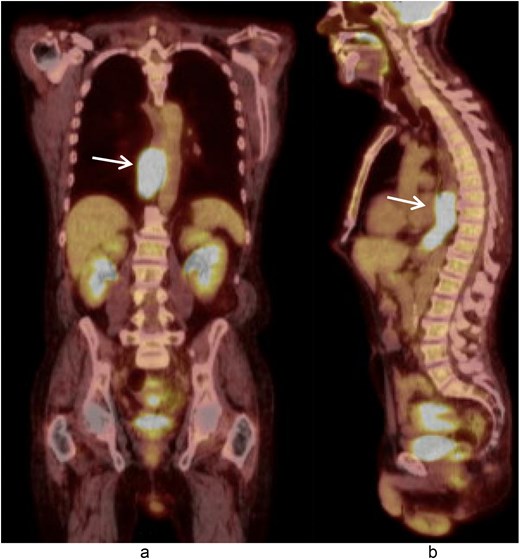

A 58-year-old male with a history of hypertension, daily alcohol use, and 35 pack year smoking history presented with progressive dysphagia and significant weight loss over a period of 3 months. His symptoms began with heartburn, with initial failure of empiric treatment for reflux. He then developed dysphagia to solids that progressed to liquids and eventually an inability to tolerate his own saliva. Over that timeframe, he also noted unintentional weight loss of ~30 lbs. He eventually presented to the emergency department where a CT scan raised concern for an obstructing esophageal mass (Fig. 1). He urgently underwent upper endoscopy revealing a large polypoid tumor with a broad base located in the lower esophagus (Fig. 2). Biopsies revealed a high-grade malignant neoplasm with spindle cell features concerning for a sarcoma. Further workup with brain MRI and positron emission tomography (PET) scan confirmed a hypermetabolic esophageal mass without evidence of distant metastatic disease (Fig. 3). Unfortunately, endoscopic ultrasound was unable to be performed given the nearly obstructive nature of the tumor.

Coronal (a) and sagittal (b) views of the initial CT scan at time of presentation that revealed a large esophageal mass with concern for complete obstruction (arrows).